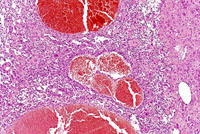

This hemangiosarcoma is well demarcated from the normal hepatic parenchyma; sharp demarcation is an unusual feature of hemangiosarcomas. Large blood-filled lakes are apparent. Higher magnification shows bands of spindle-shaped endothelial cells with attendant destruction of hepatocytes, proliferation of plump endothelial cells, and atrophy of hepatocytes.